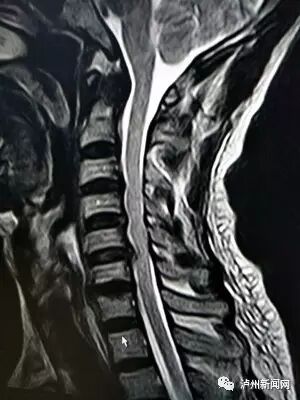

颈椎片子正常颈椎图,颈椎生理曲度变直图片

颈椎核磁共振片子

颈椎,胸椎,腰椎阅片技巧

教学看会颈椎核磁图

颈椎x光片怎么看

颈椎ct看片教程